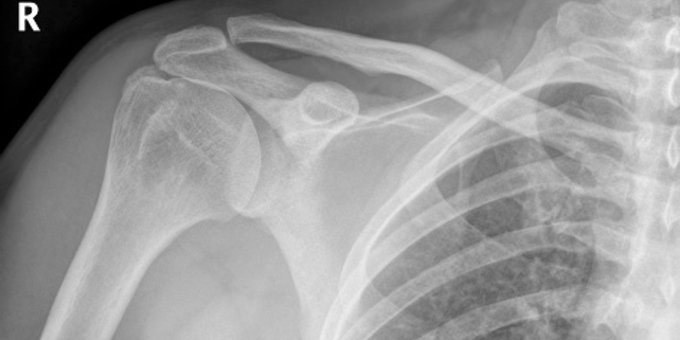

Tu manguito de los rotadores del hombro está hecho de músculos y tendones, cuyos problemas pueden incluir tendinitis, bursitis y lesiones como desgarros. Causas, tratamientos y más aquí ow.ly/XeD350BB3dA